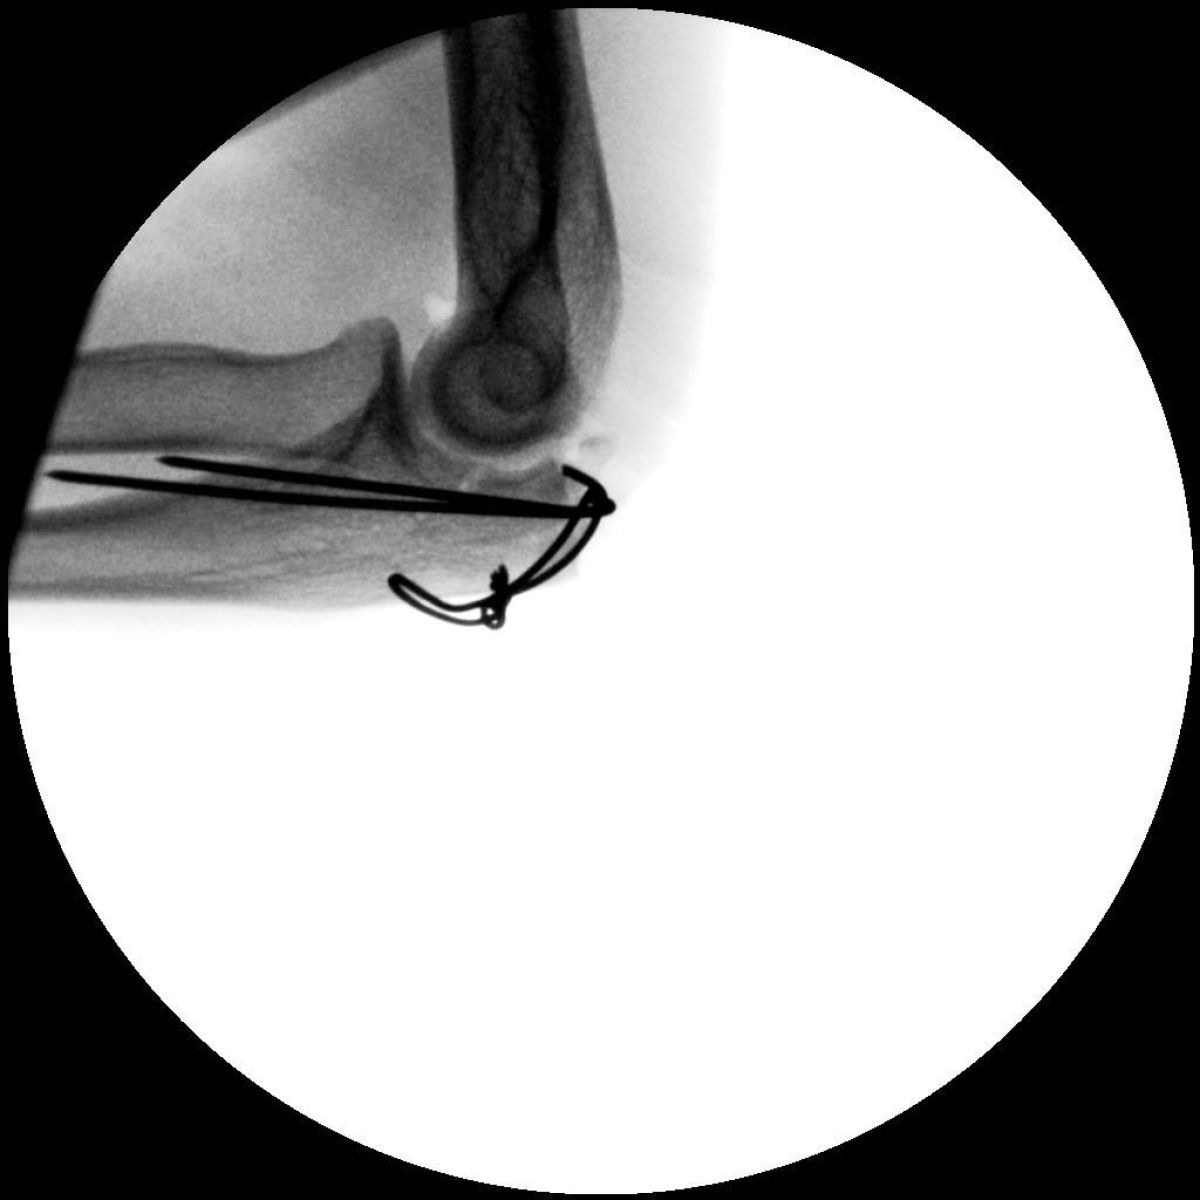

Zdaj se je Robi oboževalcem javil iz bolnišnice. Prestal je namreč 45-minut dolgo operacijo, med katero so mu iz komolca odstranili kovino. "Zadnje dejanje zgodbe o levem komolcu. Odstranitev kovine je trajala 45 minut. Počutje odlično. Popoldan trening?" se je na facebooku pošalil neuničljivi Robi in objavil fotografije odstranjenih delov kovine. Njegova žena Špela mu je povratku domov obljubila čaj. Za hitrejše okrevanje.